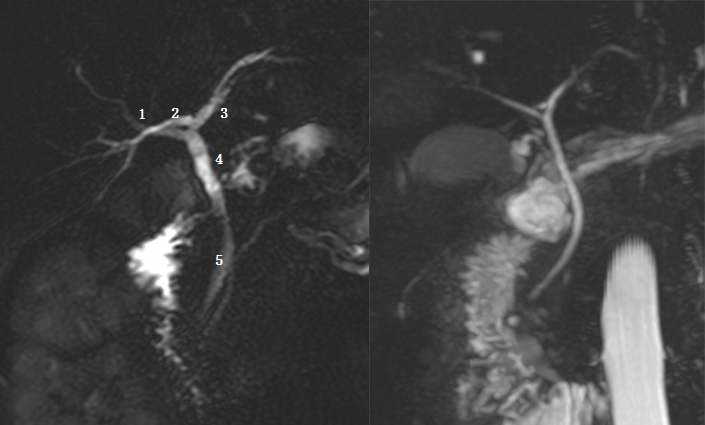

Ⅰ型:肝左右管汇合肝总管,胆囊管与肝总管汇合胆总管。左图:1 为肝左管,2 为肝总管,3 为胆囊管,4 为肝右管,5 为胆总管。黑箭头为胆囊结石。